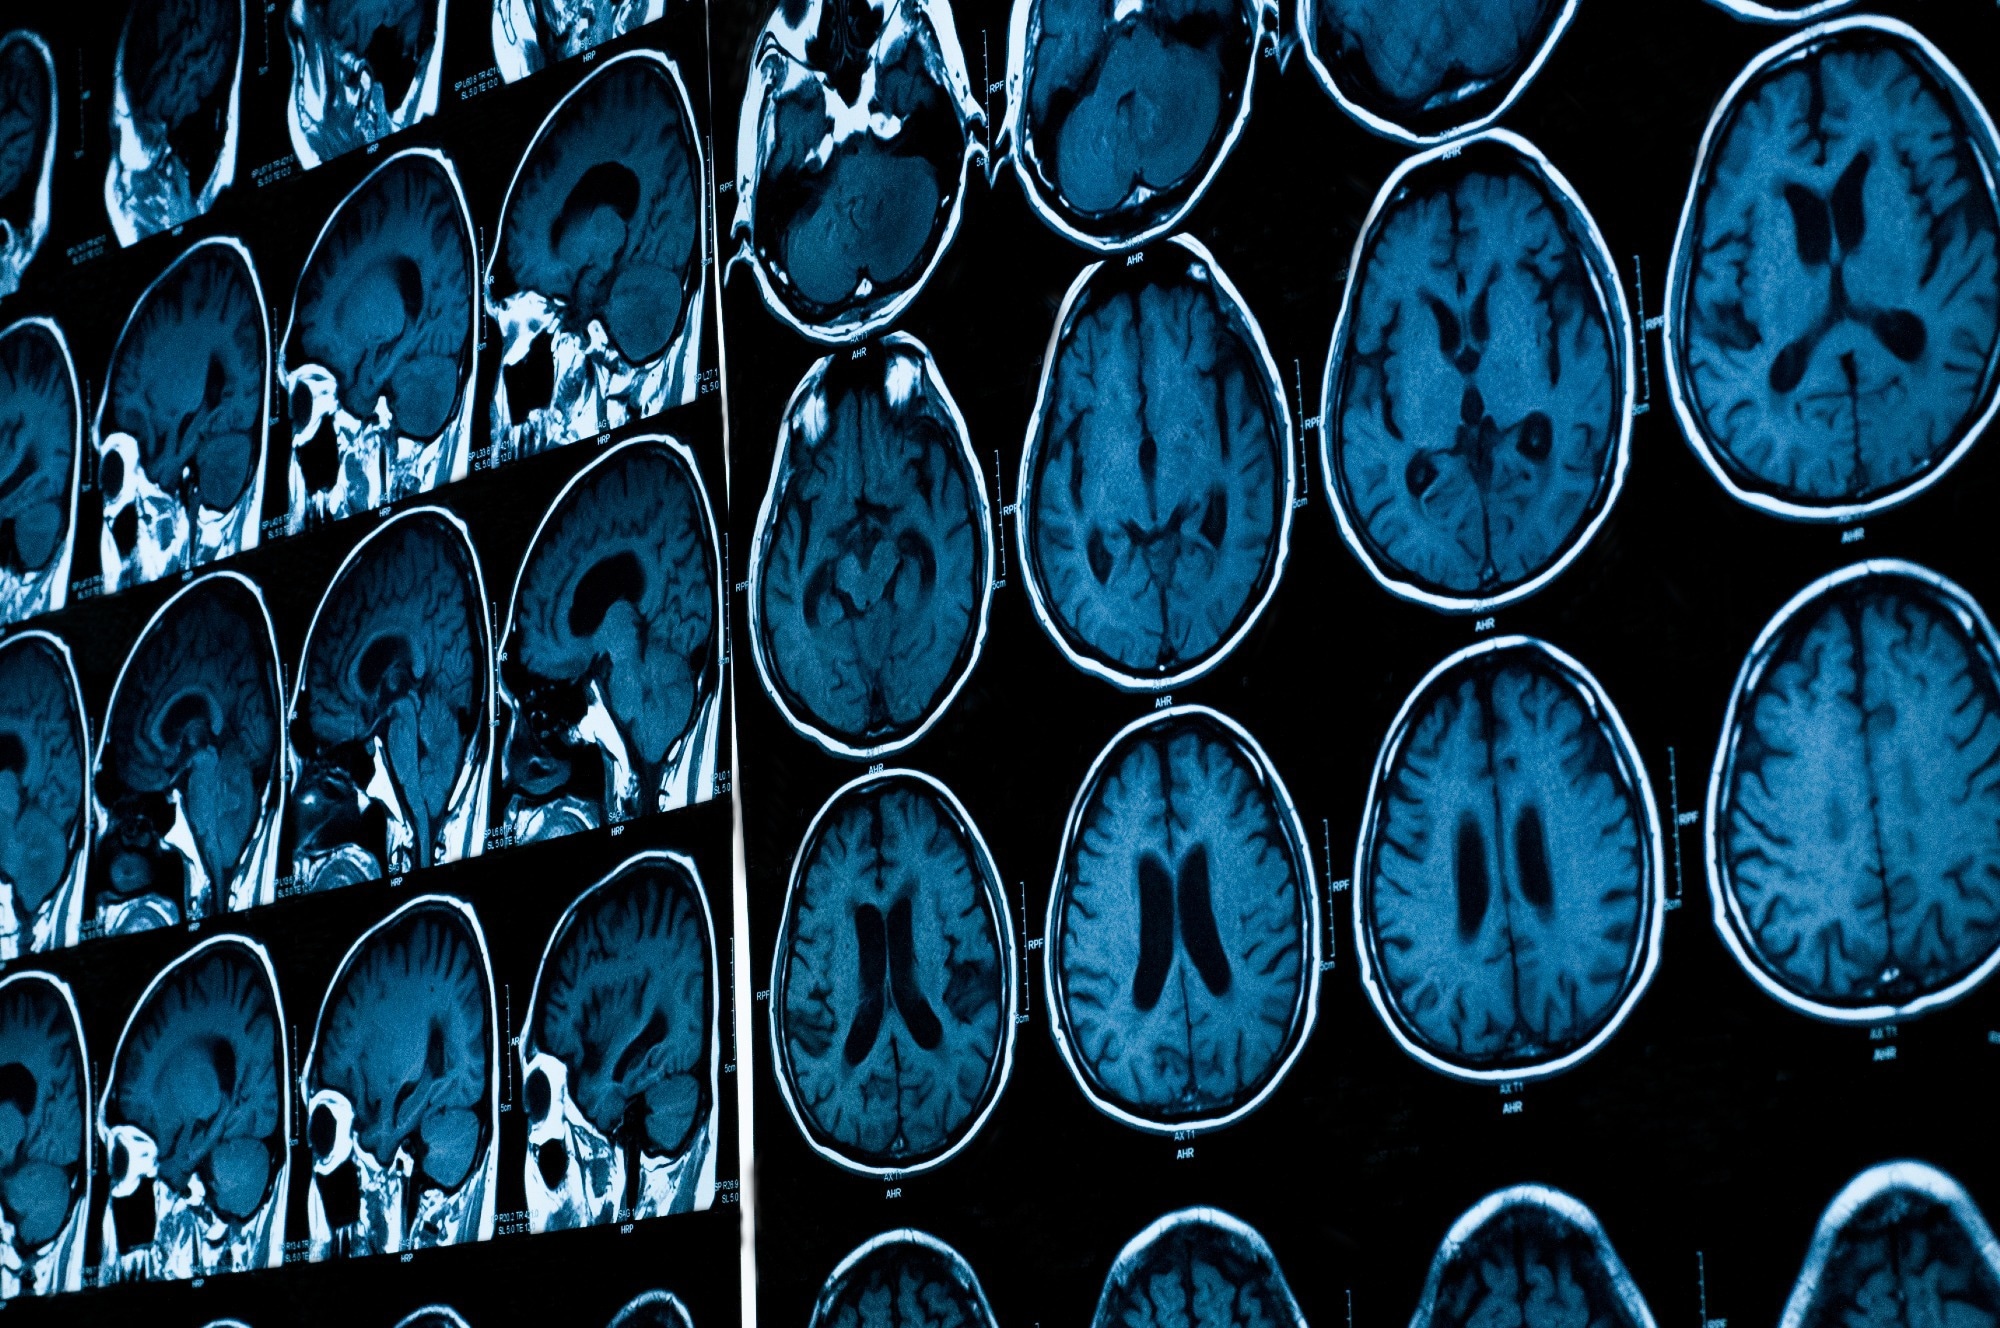

Study: Adverse Life Experiences and Brain Function: A Meta-Analysis of Functional Magnetic Resonance Imaging Findings. Image Credit: Tushchakorn / Shutterstock.com Study: Adverse Life Experiences and Brain Function: A Meta-Analysis of Functional Magnetic Resonance Imaging Findings. Image Credit: Tushchakorn / Shutterstock.com